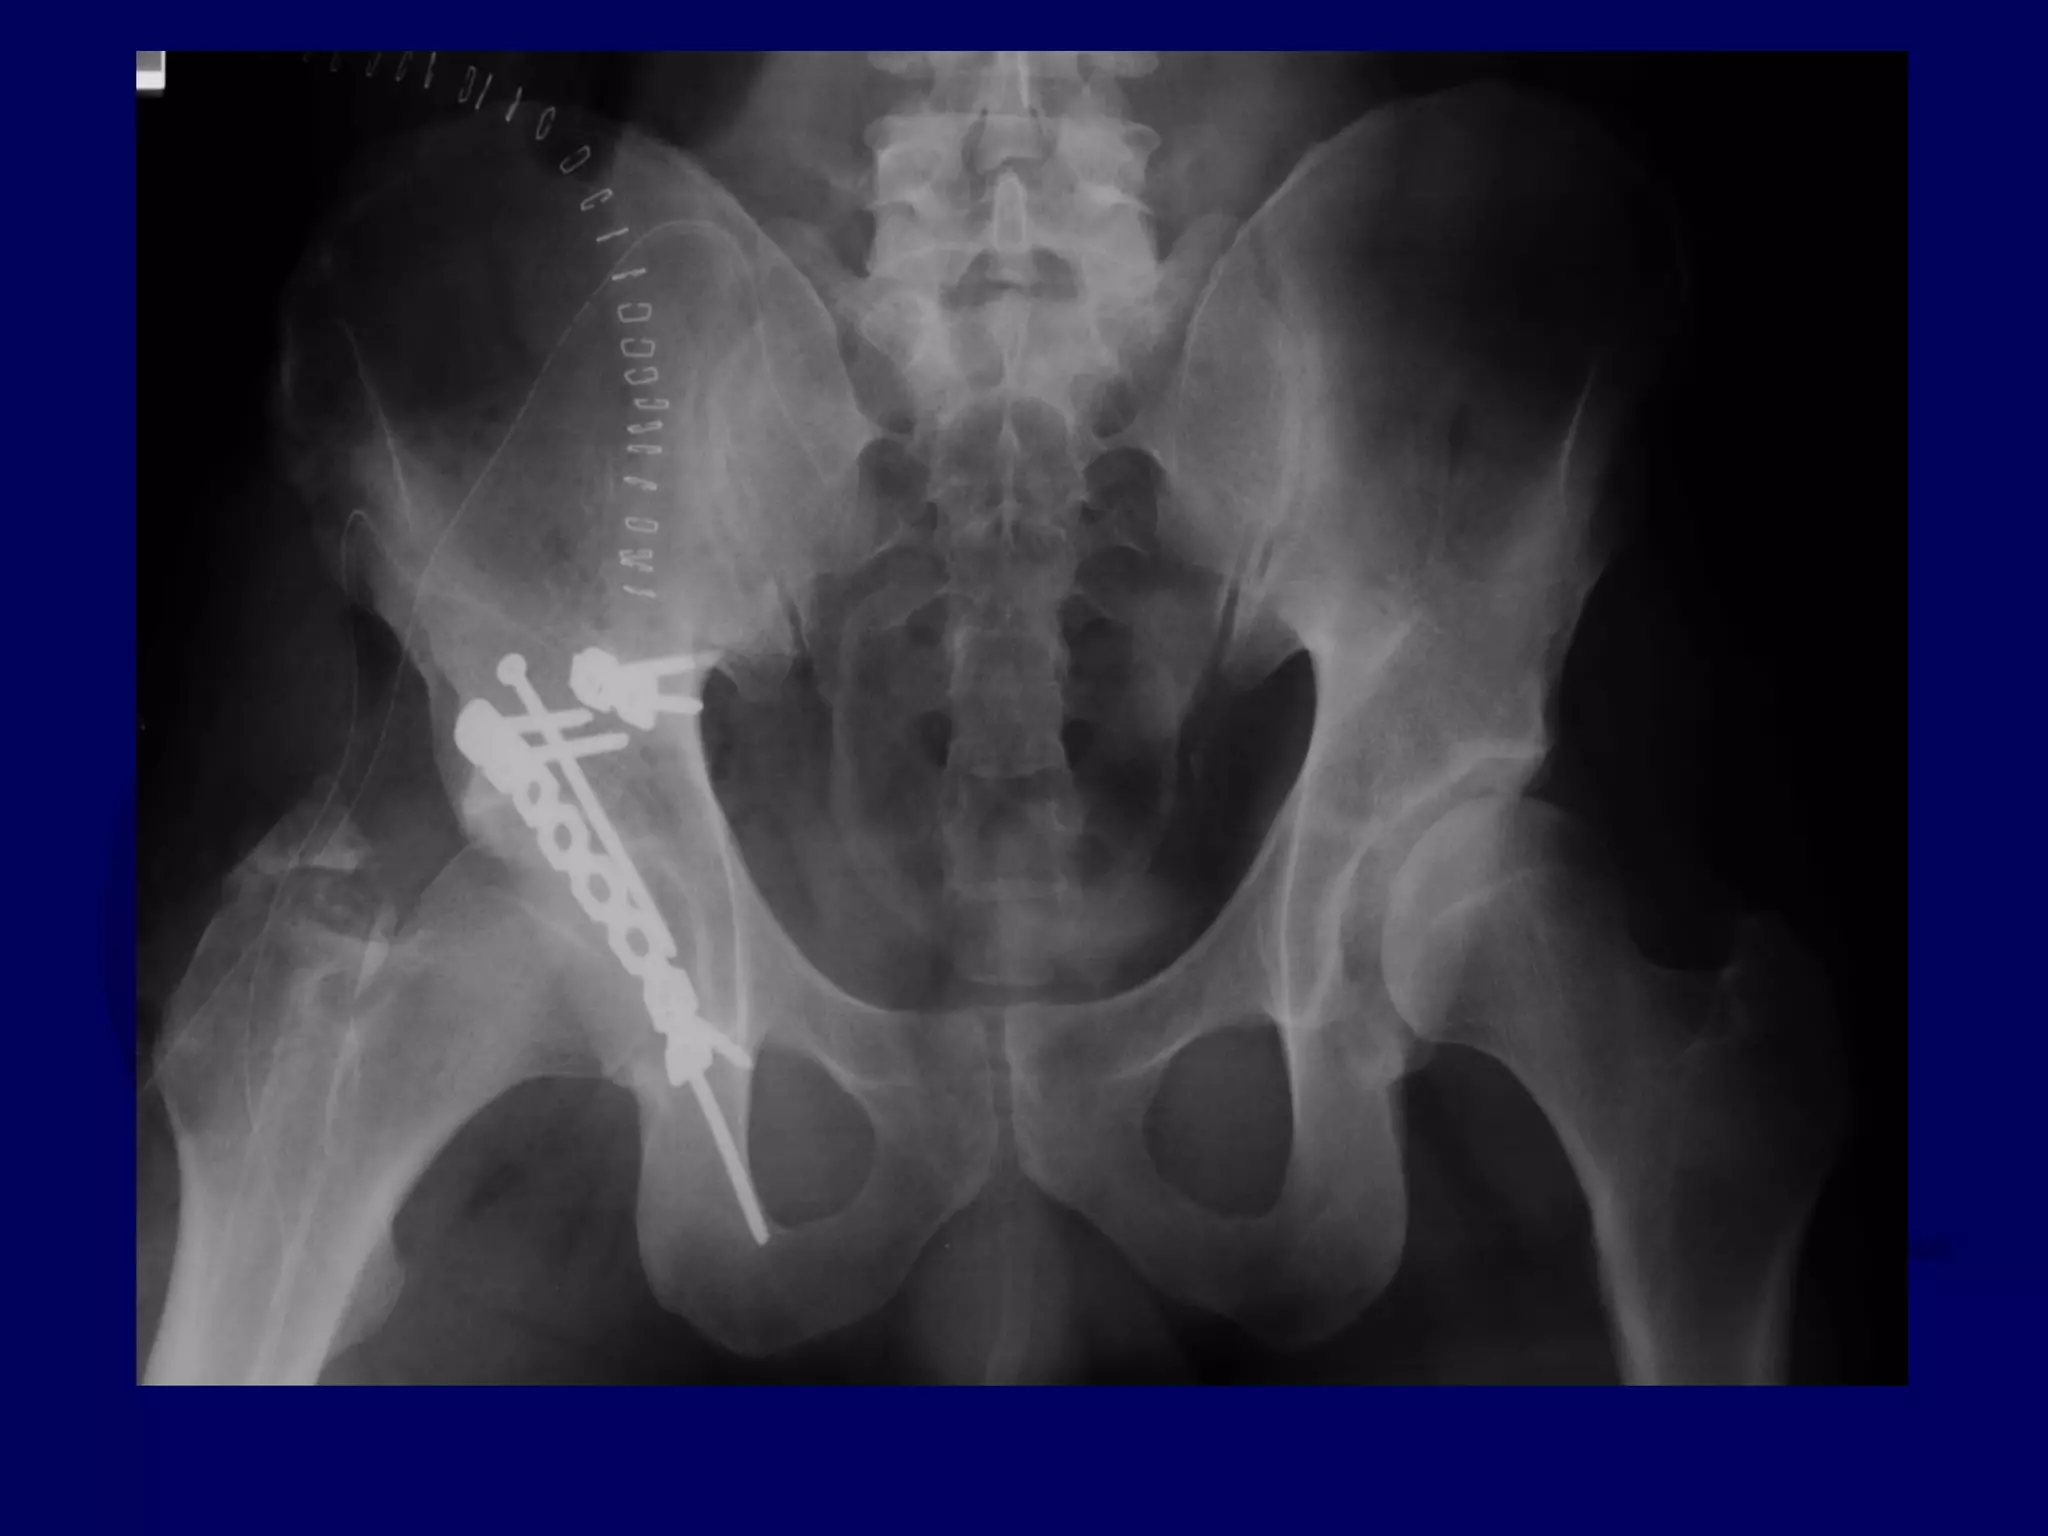

Special Case

“T-Type” Acetabular Fracture

Proximal Femur Fracture

14 y.o. Male

Sequential K-L / Ilioinguinal

Approaches

P.J. 00.12.16

Initial Kocher-Langenbeck

Approach

P.J. 00.12.18

Subsequent Ilioinguinal

P.J. 00.12.22